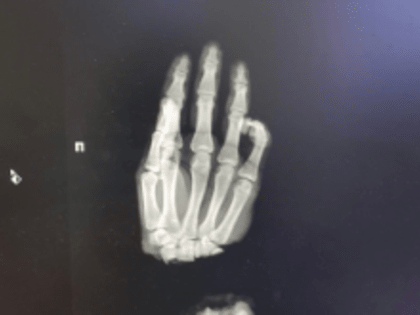

Нижегородские врачи спасли руку 16-летнему подростку

16-летний парень из Владимирской области оказался в нижегородском медучреждении, после того как случайно отрубил себе руку.

Нижегородские медики пришили подростку из Коврова отрубленную руку

Нижегородские медики пришили кисть подростку из Коврова. Юноша поступил в ПИМУ со страшной травмой: он отрубил себе руку, когда колол дрова.

Нижегородские хирурги пришили подростку отрубленную топором кисть

Врачи Университетской клиники ПИМУ пришили подростку отрубленную кисть. Об этом рассказал глава вуза Николай Карякин в соцсетях.